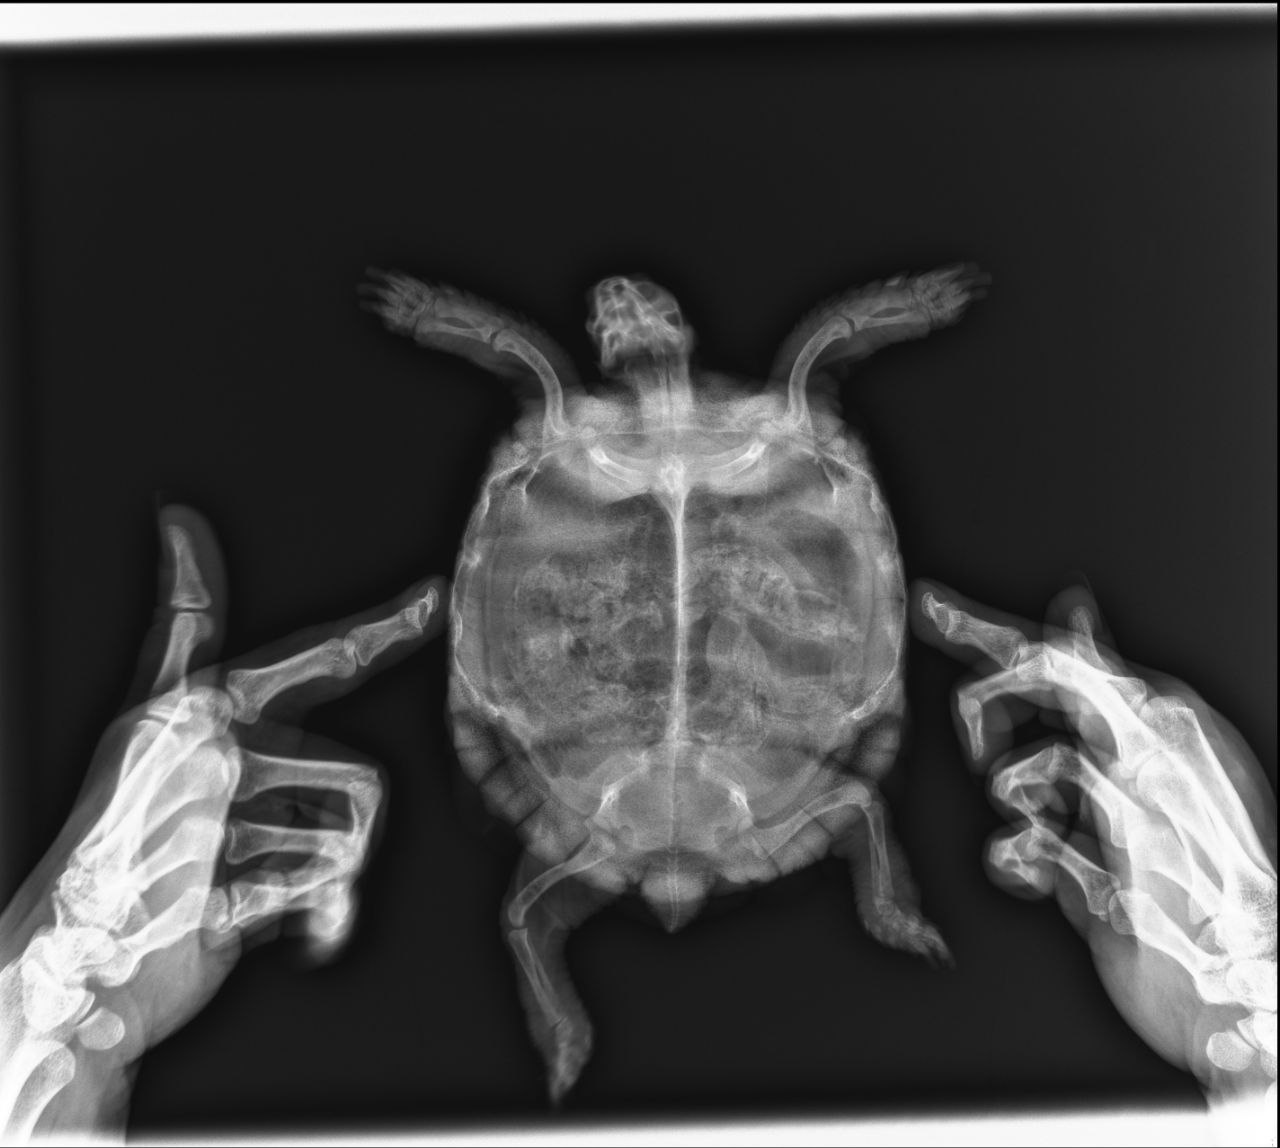

второй рентген:

vtoroi-rentgen.jpg

Во-первых в такой проекции никаких лёгких не видно, но видно, что жкт был забит газами и каловыми массами.

Для того, чтобы увидеть лёгкие нужно делать другие проекции. Поэтому лечение и диагноз были неверными. Более того, такое количество фуросемида могло добить и без того больные почки, т.к. они у всех среднеазиатов в неволе слабое место, тем более, что она раньше жила под батареей.